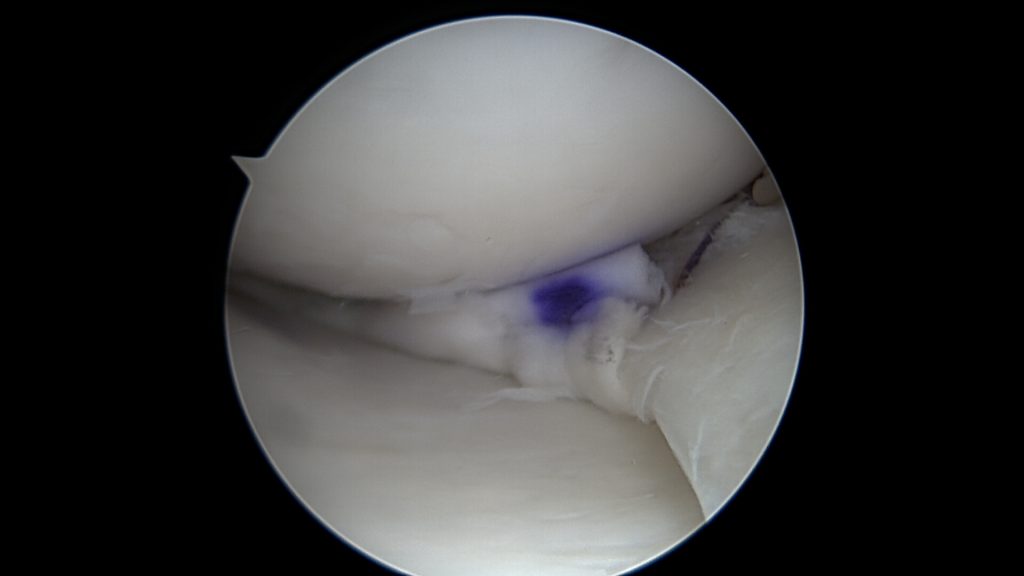

Potwierdzenie rozpoznania tego uszkodzenia następuje podczas zabiegu bardzo szybko. Zaraz po wprowadzeniu optyki do stawu po prostu widzimy łąkotkę nie tam gdzie powinna być, czyli tuż przed kamerą. Po wykonaniu inspekcji wszystkich dostępnych części stawu dokonuje się odświeżenia miejsca uszkodzenia oraz „repozycji” uszkodzonego fragmentu łąkotki (przepchnięcia jej na swoje miejsce). Następnie przy pomocy szwów zakładanych artroskopowo mocują się ją na swoim miejscu.

W tym przypadku jej proste przyszycie nie będzie możliwe, nie będzie po prostu stabilnych fragmentów łąkotki które można złapać szwem. Konieczne jest zastosowanie techniki „biokanapki”. Zabieg polega na owinięciu błoną kolagenową uszkodzonego fragmentu łąkotki, błona pełni tu rolę worka trzymającego włókna łąkotki razem. Szwy zakłada się poprzez błonę kolagenową stabilizując tym samym luźne uszkodzone fragmenty łąkotki. Na koniec zabiegu podaje się komórki macierzyste do środka stworzonej w ten sposób przestrzeni. Postępowanie pozabiegowe jest w tym przypadku określone odpowiednim protokołem rehabilitacyjnym.